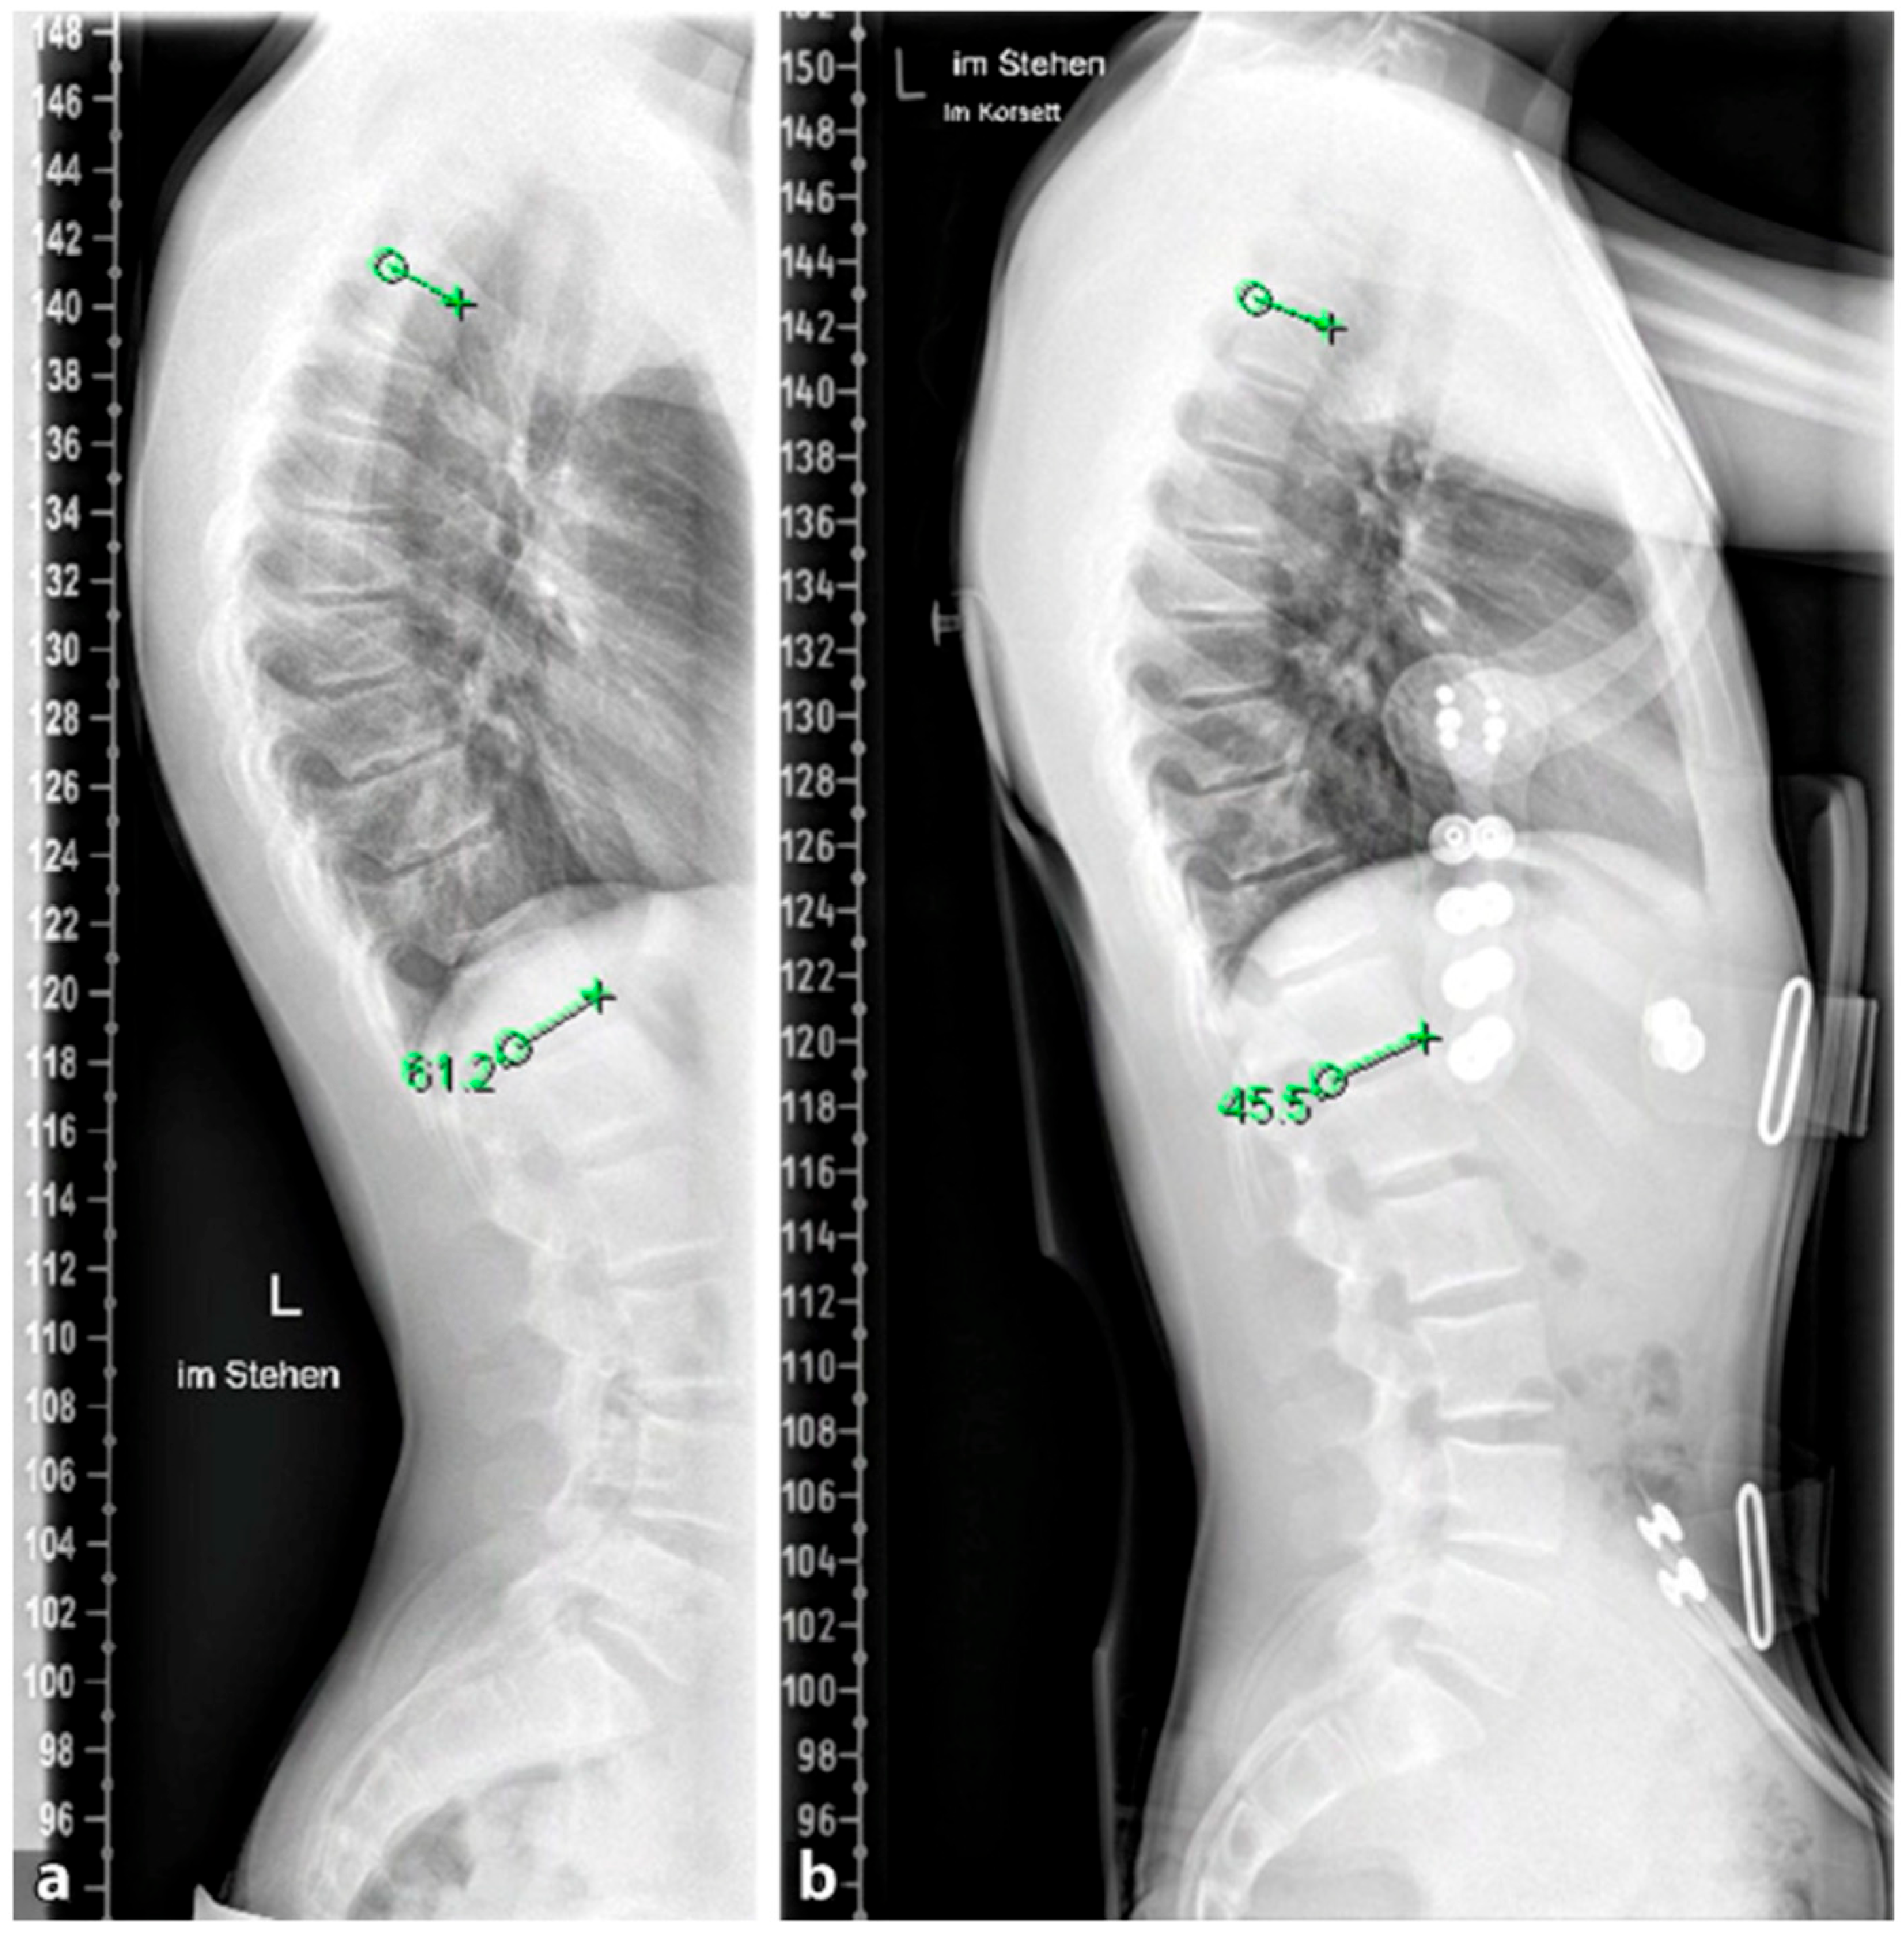

4.2. Diagnostics

Although initially described by Sorensen, the definition of SD has been definitively established by subsequent work by Edgren et al. and Blumenthal et al., with SD typically manifesting mostly in the thoracic spine (type I) and less commonly in the lumbar spine (type II) [79,85,86]; see Figure 7. The measurement of thoracic kyphosis according to Cobb (Th1–Th12) is sometimes difficult on conventional X-rays due to the humeral heads, so the Stagnara angle (Th4–Th12) is a reliable alternative (Figure 8). In children with SD, back pain and a positive family history are common, and clinical examination typically reveals a gibbus and a flexible deformity. In addition to a detailed medical history, a thorough physical examination is of utmost importance. The various signs and findings typical of SD are listed in Table 2.

4.3. Conservative Therapy

The goal of orthopedic treatment is to relieve pain by reducing pressure on the anterior aspect of the vertebral endplates. In addition, it can facilitate the healing of certain local lesions. The conservative treatment of SD depends on the degree of curvature. Curves under 60° are well compensable with spinal physiotherapy and other supportive measures, while curves of 60–80° respond well to brace therapy in most cases [26]; see Figure 10. For less pronounced forms (<60°), physiotherapy with extension of the spine and retraction of the scapulae and rehabilitation according to Katharina Schroth, which is also successfully applied in milder forms of scoliosis, provides good pain relief and in some cases even an improvement in kyphosis [90,91,92]. Brace therapy is well suited for curves >60°. Various types of braces show good results. The principle of correction is based on a dorsal pad with two thoracic pads that achieve a de-kyphosis of the thoracic spine.